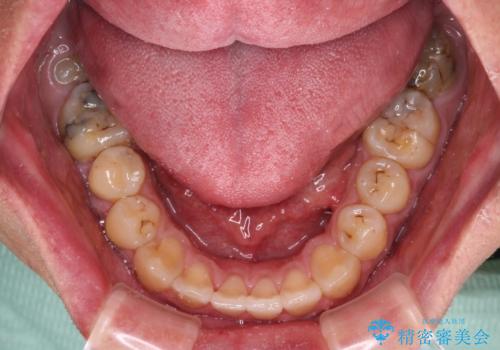

- 前歯のデコボコと上下のクロスバイトを気にして来院された患者様です。

インビザラインを用い、IPR(歯と歯の間を削る)と歯列全体を拡大させることで、歯並びを整えていくこととしました。

上の前歯が下の前歯を乗り越える際、奥歯がほとんど咬めない時期があり、乗り越えた後も、インビザライン特有の奥歯の咬みにくさが続きました。

咬み合わせ改善のために治療期間を要しましたが、最終的に奥歯はしっかりと咬めるようになりました